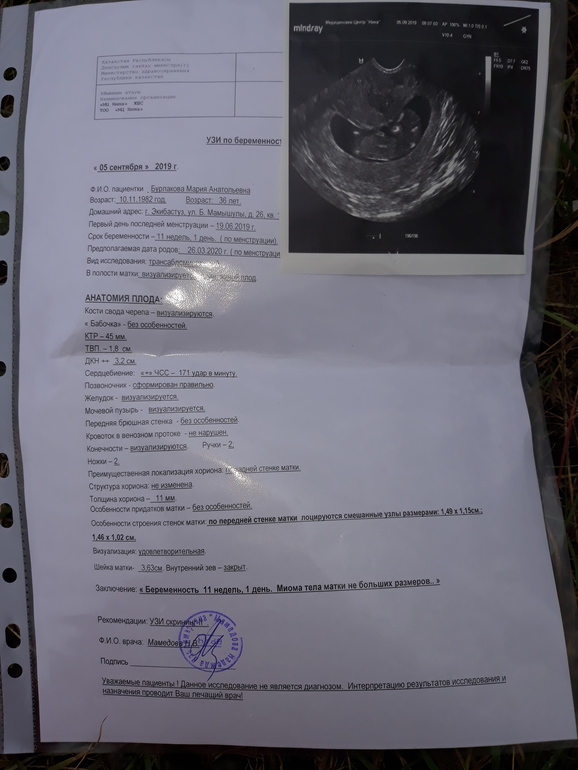

Всем привет, сегодня 12 недель по подсчетам календаря. Последние месячные 19 июня. Пришла на узи, врач сказала что еще слишком рано что по узи где то 9.5 недель. И трижды спросила про миому, небыло ли у меня ее. Я вся в растроеных чувствах, сказала прийти через 2 недели. Что может быть? Я спросила все ли впорядке? Она сказала что сердцебиение есть ручки и ножки вижу и пока что все. Вот такой скрининг, несостоявшийся. Дело в том что у меня четкий менструальный календарь все четко как в швейцарском банке, беременность не планировали но так уж вышло, у кого нибудь так было что срок по узи меньше?спасибо всем неравнодушным.

Ходили мы все же в платную клинику что бы убедится все же. Миомы подтвердились аж 2шт. Никогда их небыло, срок по узи 11 и 1. Показали малыша со всех сторон фото сделали сердечко дали послушать. Такая прелесть, я хоть чуток успокоилась. Он такой хороший малыш. Сказала ходите беременность спокойно, миомы вас не должны сейчас волновать.

Так по бэбиблогу у Вас полных 11 недель, пошла 12я. Но в любом случае для 11 недель у Вас получается, по словам узистки, плод отстаёт. Я бы Вам посоветовала пойти к другому узисту, может эта не особо разбирается. Она назвала ктр?